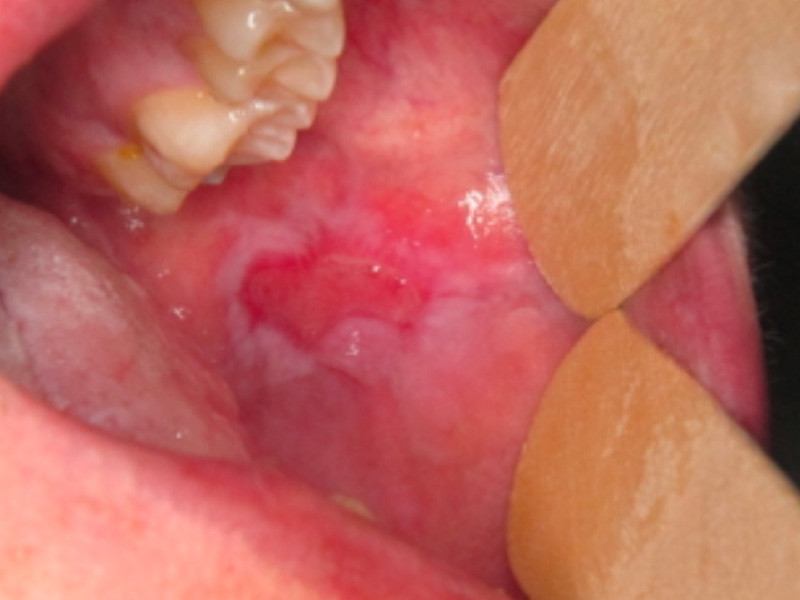

Examen clinique. Il révélait une ulcération, de 1,5 cm de grand axe, de la joue bordée par une muqueuse atrophique et kératinisée.

Synthèse. La lésion est caractéristique d’une réaction lichénoïde survenue dans le cadre d’une maladie du greffon contre l’hôte (Graft-Versus-Host Disease, GVHD).

La GVHD est l’une des principales complications de l’allogreffe de cellules souches hématopoïétiques. Elle est secondaire à une réaction des cellules immuno-compétentes du donneur contre les cellules du receveur. Les lésions buccales de la GVHD ont une grande ressemblance clinique et histologique avec le lichen plan idiopathique. Le contexte de survenue permet de faire le diagnostic.